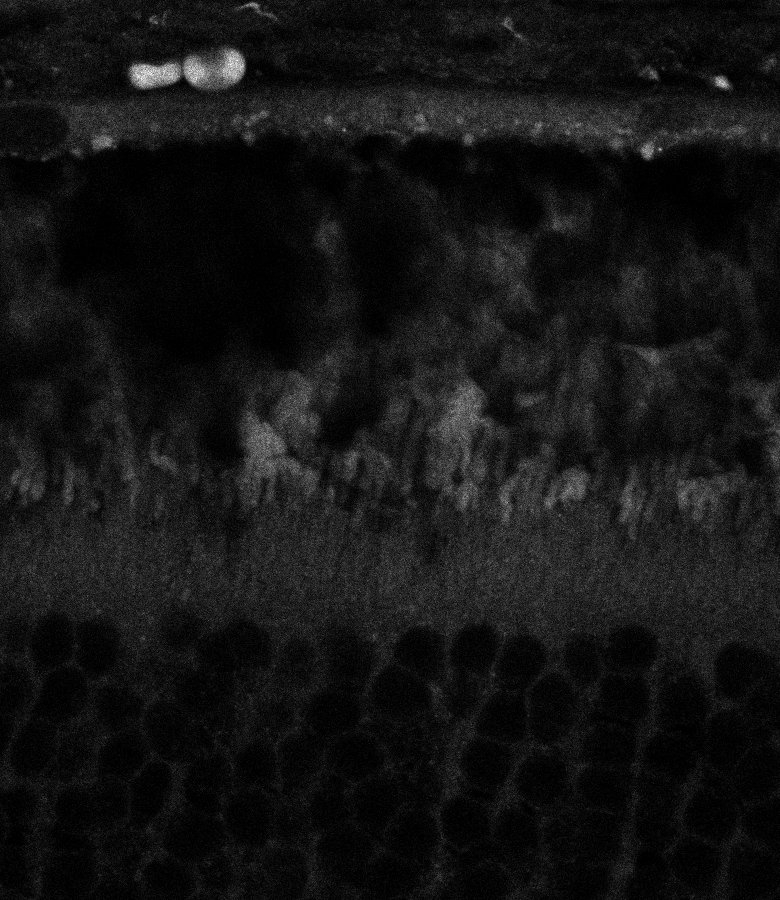

Unhealthy Retina

Unhealthy Choroid